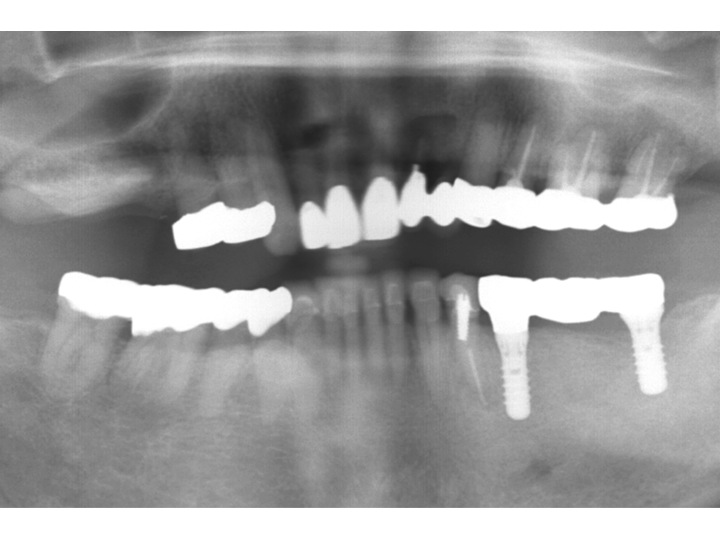

インプラントオンライン見積もりは こちらをクリック

欠損部からインプラントの治療費や治療期間(治療回数)等をお答えします。